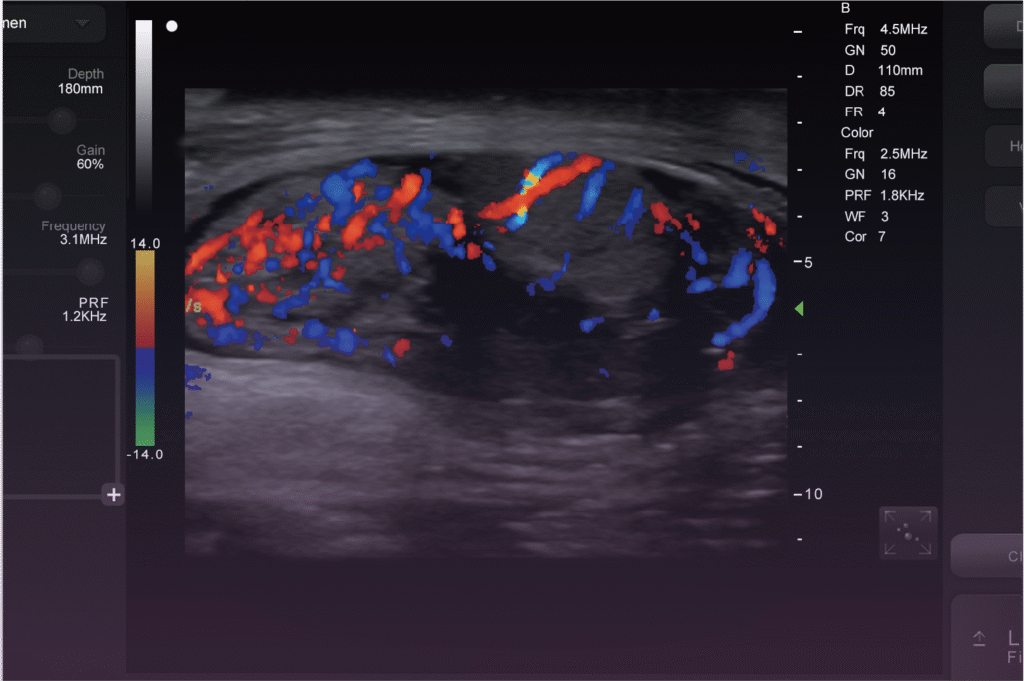

Looking to identify non-pregnant cows more quickly? BestScan’s color flow Doppler mode allows you to detect them earlier, potentially saving you up to 3.5€ per cow per day. With its intuitive interface and cutting-edge features, ImaGo optimizes your workflow, minimizes downtime, and boosts flexibility—ensuring you remain efficient no matter where your work takes you. “42% Faster Than Our Old System – Caught Twin Calves Every Rancher Missed!”— Dr. Sarah McLeod, Hoof & Horn Mobile Veterinary

The versatile probes, including 128/192-element curved and linear options, are perfect for bovine veterinarians who frequently move between farms and work with various species. Additionally, iBtech technology facilitates seamless connections to mobile devices and goggles, making it easy to share images, conduct training sessions, or engage with clients effectively. This innovative approach enhances your workflow and ensures you can provide top-quality care wherever you are.

Tailored for bovine and mixed-practice veterinarians on the go, BestScan Series offers unmatched accuracy and user-friendly operation. With its durable, portable design and superior image quality, you can always be prepared to deliver top-level care, regardless of how many farms you visit or how hectic your schedule may be. Stay ready to provide exceptional service wherever your work takes you!